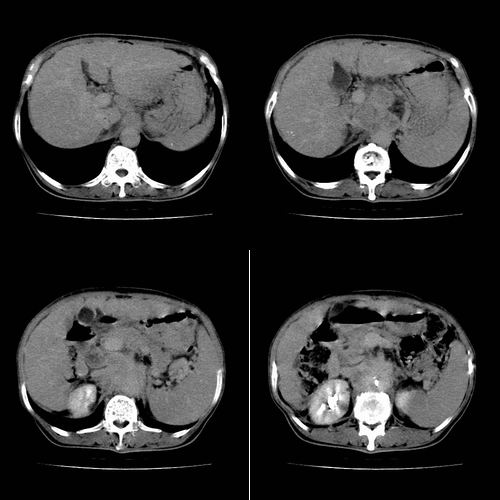

患者 女性 58岁,家族有乙肝病史,(并姊妹中已有3人确诊肝癌,真是不幸!乙肝病毒真是害死人!)近期明显消瘦,乏力,右上腹疼痛.行ct结果非常典型,请诸位老师会诊!

图片非常漂亮!肝内病灶符合较典型肝癌的强化方式,速升速降,其内可见坏死,腹膜后示肿大淋巴结融合成团,包绕腹主动脉、腹腔干动脉、肠系膜动脉。右肾小囊性病灶,未见明显强化。

诊断:肝癌并腹膜后淋巴结转移。

肝癌伴腹膜后淋巴结转移,肝硬化伴脾大,好像没有发现门静脉及下腔静脉瘤栓形成.

根据增强的特点看,应该是肝癌,腹膜后胰头区低密度占位应该是腹膜后淋巴结增大,多考虑转移

肝癌伴腹膜后淋巴结转移,肝硬化伴脾大,好像没有发现门静脉及下腔静脉瘤栓形成.看腹腔干是不是有浸润

1、肝右叶肝癌,后腹膜淋巴结转移(包绕腹腔干及肠系膜上动脉,推压门静脉、下腔静脉及胰头)

2、肝硬化、脾肿大

3、右肾小囊肿

1、肝硬化,脾肿大

2、肝癌,动静脉瘘(动脉期门静脉内造影剂进入)

3、后腹膜淋巴结转移,下腔静脉推移